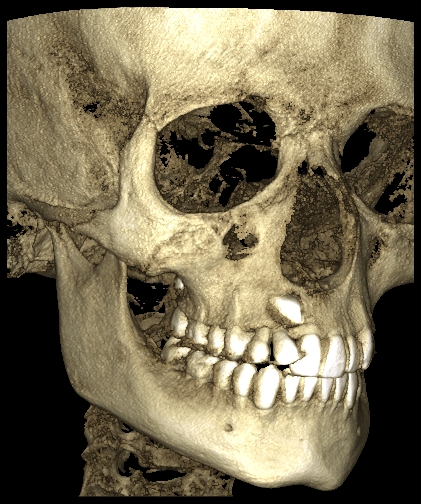

CBCT

La Tomografia Computerizzata Cone Beam è stata adottata nel nostro studio per l'imaging diagnostico 3D nel 2010.

Non viene utilizzata di routine ma solo in casi complessi seguendo sempre il principio ALARA (As Low As Reasonably Achievable=Esposizione alle radiazioni X il più basso possibile in accordo alle esigenze diagnostiche e terapeutiche).

Nella routine, la stessa apparecchiatura consente la presa di immagini digitali 2D a basso livello di esposizione radiologica.